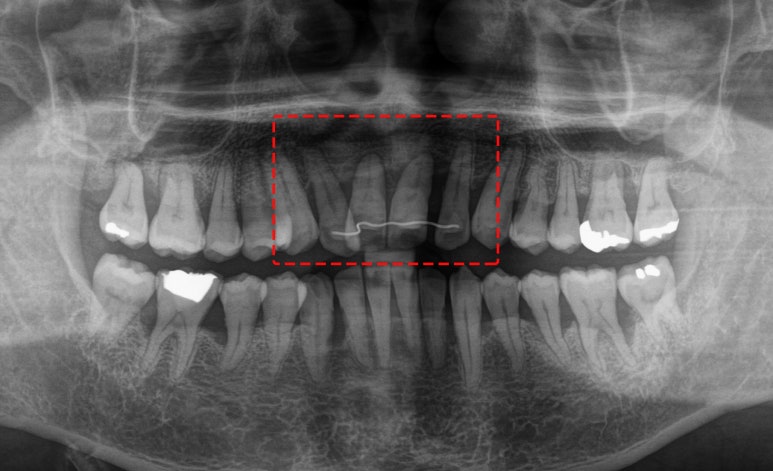

파노라마를 살펴보면

유지 장치를 부착해둔 이들이 보입니다.

그런데 뿌리 끝으로 염증 소견도 있고

그리 건강해 보이지만은 않습니다.

아마도 위 아랫니가 지속적으로

닿으면서 자극이 되고,

계속된 스트레스와 함께 잇몸뼈에도

영향을 준 것 같습니다.

어떻게 해야 될까요?

보라매 치과 에서는

이렇게 치아 뿌리 상태가 양호하지 않은 채로

무리한 교정을 진행하지 않습니다.

자칫하면 치아의 동요도가 커질 수 있기에

여러 조건을 세밀하게 따져가며 해야 됩니다.

그래서 이 환자도

치아 교정 대신

임플란트와 브릿지 보철을 통해

이 문제를 해결하기로 했습니다.

이것으로도 충분히

가능할 것이라 판단했기 때문이죠.